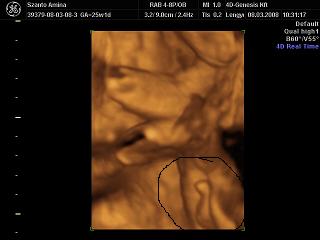

És egy tappancs 2008.03.08 19:45